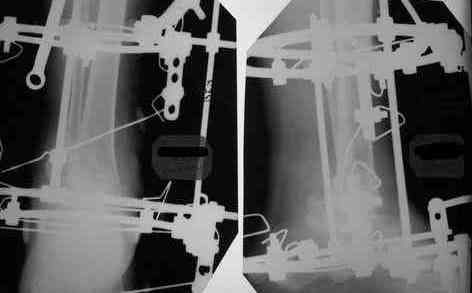

Уважаемые коллеги. Тема обсуждалась: Прошу прощения за задержку с ответом. Женщину прооперировал. Из внутреннего доступа удалена внутренняя лодыжка, из наружного отсечена от рубцов латеральная, из обоих параллельно предыдущей остеотомии экономно произведена резекция "суставных" поверхностей ББК и тарана до "кровавой росы", удалены все рубцы, стопа выведена, провизорная диафиксация спицами. Далее аппарат, однако, после удаления диафиксирующих спиц и компрессии, произошло наружное смещение тарана. Но и так время операции составило почти 4 часа, поэтому через неделю пришлось маленько подработать аппаратом. Итог на снимках (извиняю сь за качество). Не совсем все нравится - в литературе намного красивее. Только один вопрос к уважаемому форуму: что действительно необходимо подправить? Спасибо. С уважением, А.Минервин.

Стопа сильно смещена кзади, если не ошибаюсь из-за маленького размера снимка.

Александр Николаевич! Постарался переделать рентгенограмму - не знаю лучше ли стало- снимки никудышные:(

Смещение стопы кзади видно более отчетливо. Это намеренно так сделано, поскольку так сформировались контактные поверхности?